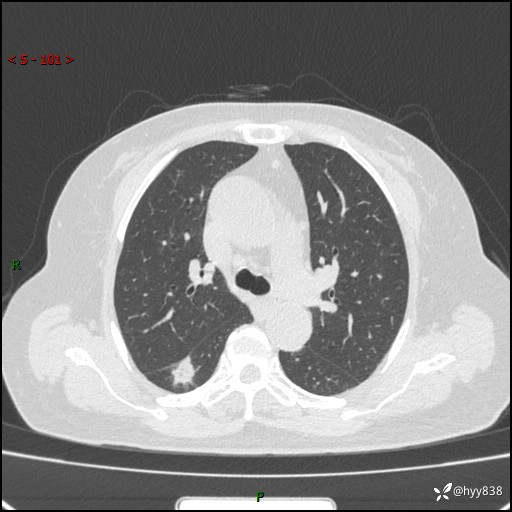

71岁/女,发现肺结节1月。偶然发现孤立肺结节,邻近叶间裂凹陷---结果公布(再回首)

【患者信息】:71岁/女

【主诉】:发现肺结节1月

【现病史及既往史】:2024年9月患者因“胆囊结石”于我院肝胆外科住院,期间完善胸部CT提示:右下肺结节灶,高危结节?感染?,病程中无畏寒发热,无咳嗽、咳痰,无活动后气短,无心慌胸闷,无胸痛、咯血,无头晕头痛,无腹痛腹泻,无四肢肌肉酸痛等不适,当时建议其择期复查。今日患者为求进一步复查就诊于我院,完善胸部CT提示:右肺结节,较前一致,遂门诊“肺部结节”收入我科。 自本次起病以来,患者精神、饮食、睡眠可,大小便正常,体力、体重未见明显异常。

【检查】:胸部CT平扫+增强